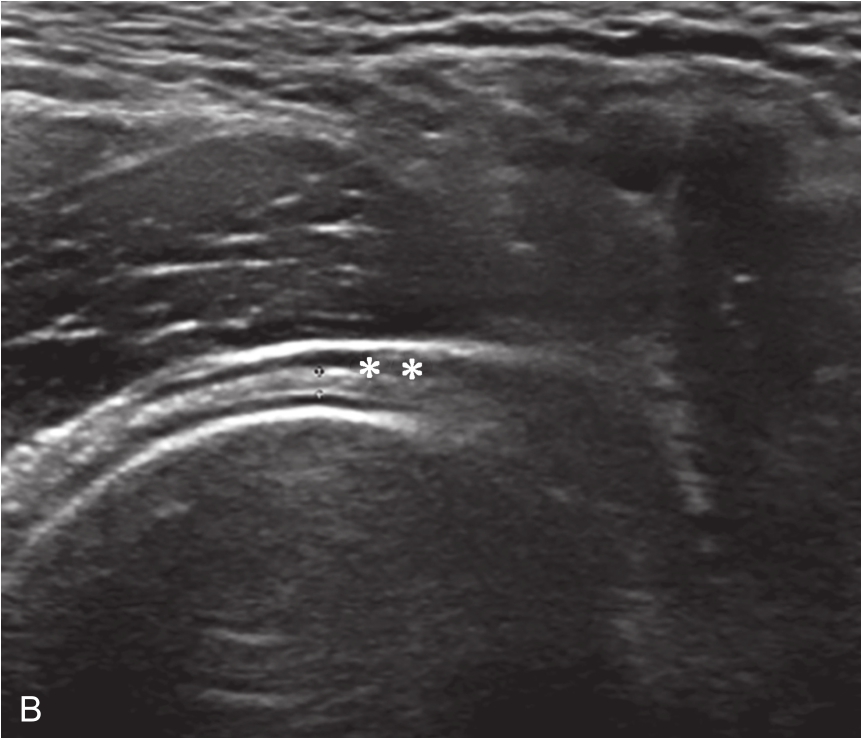

▲ 图2-6-5 超声引导下肩关节腔介入治疗超声图(三)

A.患侧肩关节下关节囊增厚;B.对侧正常关节囊;C、D.注射治疗后扩张的关节腔内粘连带;双星号:关节囊;箭头:粘连带;单星号:关节腔